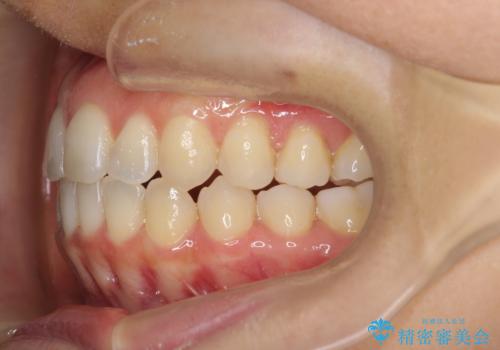

前歯のガタつきをマウスピースで治したい!

- 気になる前歯のガタつきをマウスピースで治療したいと希望され来院されました。

当日に矯正検査を行い、骨格・歯に問題がないことを確認しマウスピースによる矯正治療を進めます。

IPRを前歯部に少量行うことで、非抜歯でも前歯が外に飛び出さない仕上がりを達成できました。